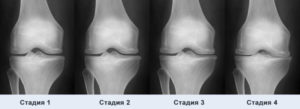

Вместе с тем эта патология представляет опасность ввиду своего хронического течения – она практически неизлечима. Но даже малейшие признаки начальной стадии помогут вовремя отреагировать на проблему и снизить риск развития более опасных и тяжелых форм заболевания 2-4 степени.

Методы диагностики

Более продуктивными в выявлении болезни оказываются аппаратные методы диагностики и лабораторное исследование крови, подтверждающее наличие и объем питательных компонентов и хондроцитов.

Для выявления болезни используются:

- Артроскопия;

- Компьютерная томография;

- Магнитно-резонансная томография;

- Рентгенография;

- УЗИ.